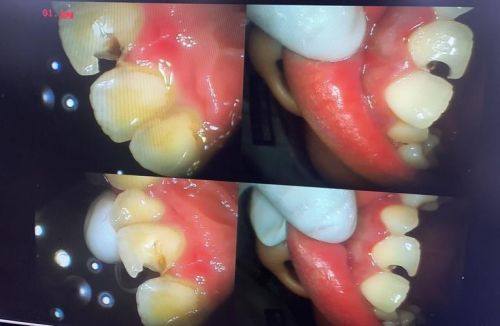

4. 牙体牙髓病治疗:配备牙髓测量仪、热牙胶充填设备等精良器械,开展根管治疗、补牙等项目,精细处理牙髓炎、根尖周炎等问题,保留天然牙功能。